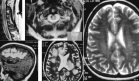

La resonancia magnética evidenció un engrosamiento cortical marcado y realce sinovial, compatibles con un pinzamiento mecánico crónico y una inflamación secundaria. Las imágenes en T1 y T2 confirmaron la afectación de la diáfisis tibial media y el compromiso del compartimento articular lateral adyacente al complejo ligamentoso lateral.